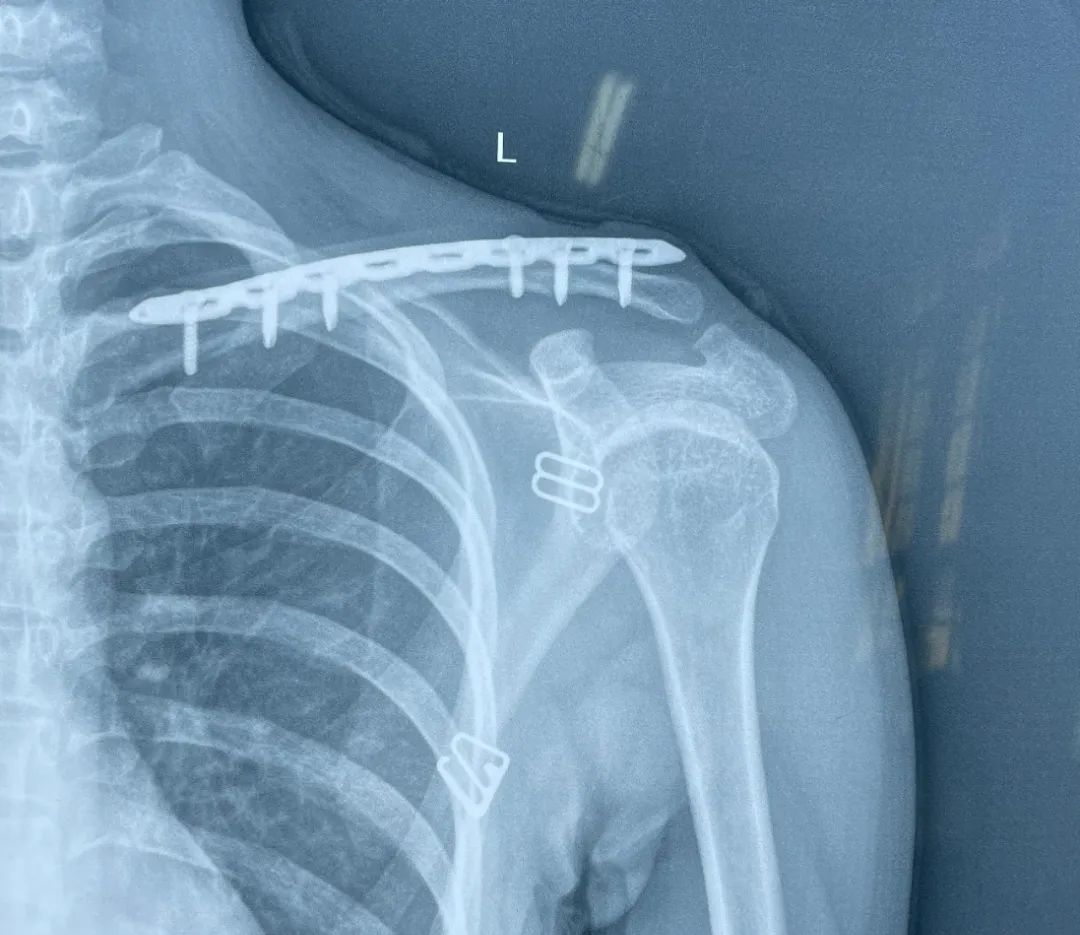

锁骨近端骨折,这样手术风险低!

锁骨近端解剖复杂,既往骨折多采用非手术治疗,预后不理想。近年来,治疗理念发生变化,手术治疗越来越多,本文整理了胸锁钩钢板在锁骨近端骨折的应用,供大家参考。